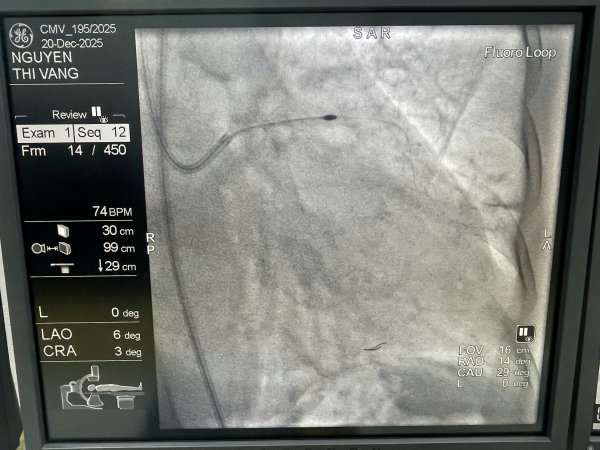

Đầu mũi khoan thế hệ mới nhất RotaPro trong lòng động mạch vành.

Trong trường hợp này, các y, bác sĩ đã sử dụng hệ thống khoan mảng xơ vữa thế hệ mới RotaPro, với mũi khoan kim cương quay tốc độ rất cao, nhằm bào mỏng và tái cấu trúc mảng vôi hóa, giúp lòng mạch trở nên mềm hơn, tạo điều kiện cho nong bóng và đặt stent tối ưu, an toàn. Quá trình can thiệp được hướng dẫn bằng siêu âm trong lòng mạch (IVUS), cho phép đánh giá chính xác mức độ vôi hóa, vị trí tổn thương và kết quả sau can thiệp. Thủ thuật diễn ra an toàn, kiểm soát tốt huyết động, không ghi nhận biến chứng, người bệnh ổn định sau can thiệp.